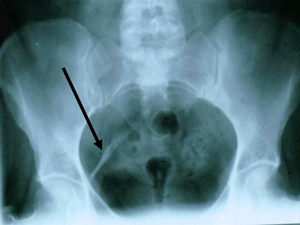

DISH is Diffuse Idiopathic Skeletal Hyperostosis.

DISH generally affects at least 2 or more levels of the spine, and most often, 97% of cases, affects the thoracic spine.